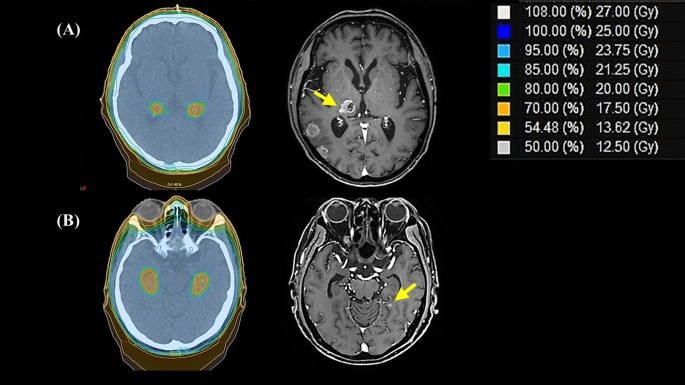

Among patients who received HA-PCI and experienced intracranial failure, two developed brain metastasis in the peri-hippocampal area (Fig. 2), and they developed intracranial failure 17 and 3 months after HA-PCI. Both patients had N3 disease at initial diagnosis, received six chemotherapy cycles, and showed partial response (PR) after the initial treatment. The mean irradiated doses to the peri-hippocampal recurrent tumor were 24.8 and 23.6 Gy, respectively, and the minimum doses were 14.8 and 21.6 Gy, respectively (Fig. 2). In the C-PCI group, only 1 patient showed peri-hippocampal recurrence at multiple other intracranial sites (> 9).

Radiation dose distribution and sites of intracranial failure (ICF) in two patients with peri-hippocampal recurrences after hippocampal-avoidance prophylactic cranial irradiation. Patient (A) was a 73-year-old man, and ICF developed 17 months after HA-PCI. Patient (B) was a 60-year-old man, and ICF developed 3 months after HA-PCI.

Although the log-rank test results were not significant (p = 0.215), as shown in Fig. 2, the intracranial failure rate might increase in the HA-PCI group with longer follow-up. However, in two patients with recurrence in the peri-hippocampal area in the HA-PCI group, the lesions occurred at margins, and one of them received a sufficient radiation dose (mean dose, 23.6 Gy; minimum dose, 21.6 Gy)14. Therefore, the recurrence could not have been because of HA. Based on our findings, whether HA-PCI increases intracranial failure should be carefully assessed.